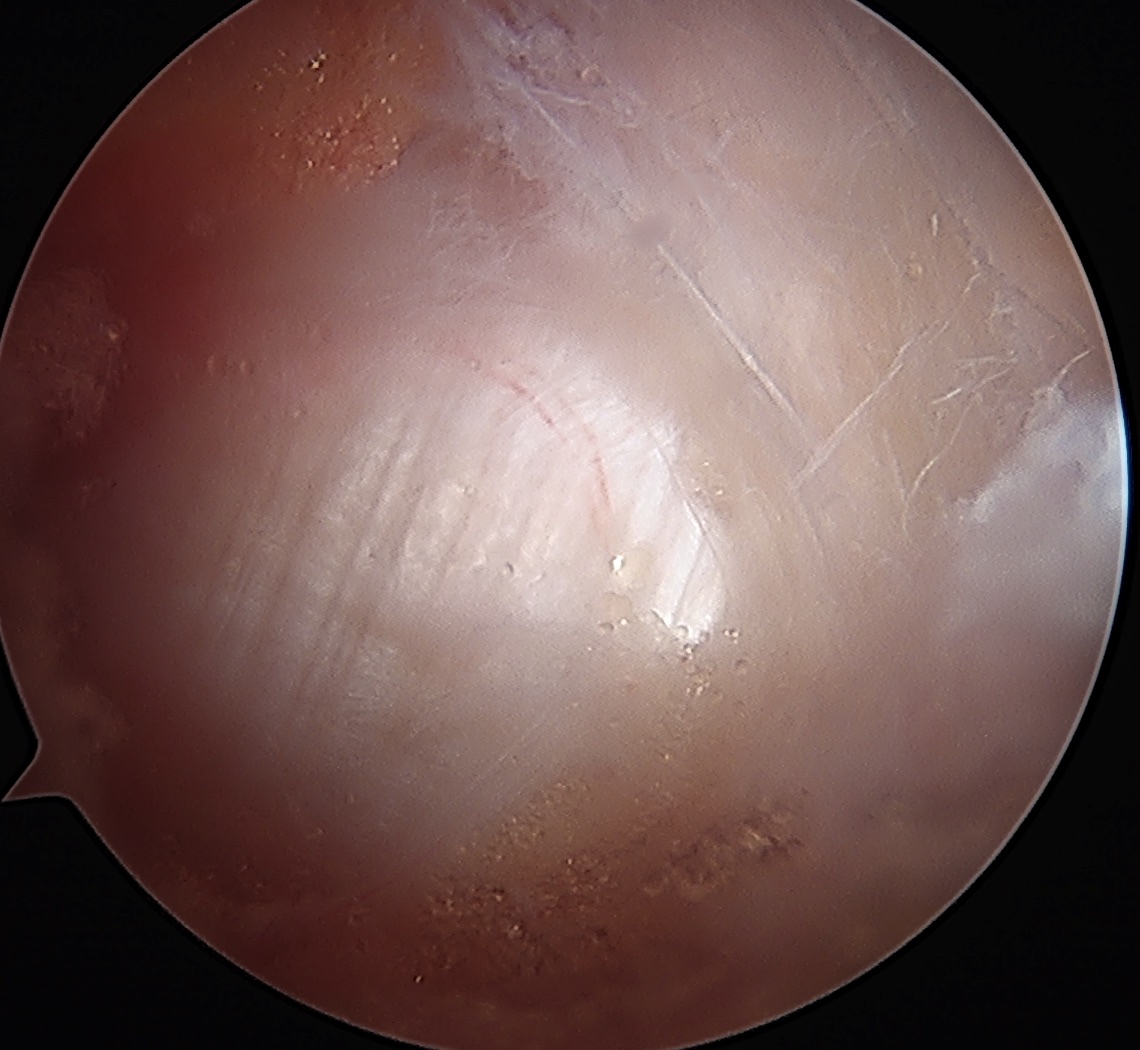

ITB vertical split / cruciform release + trochanteric bursectomy

Arthroscopic technique article

ITB band Longitudinal split

Cruciform release anteriorly Bursectomy over abductors